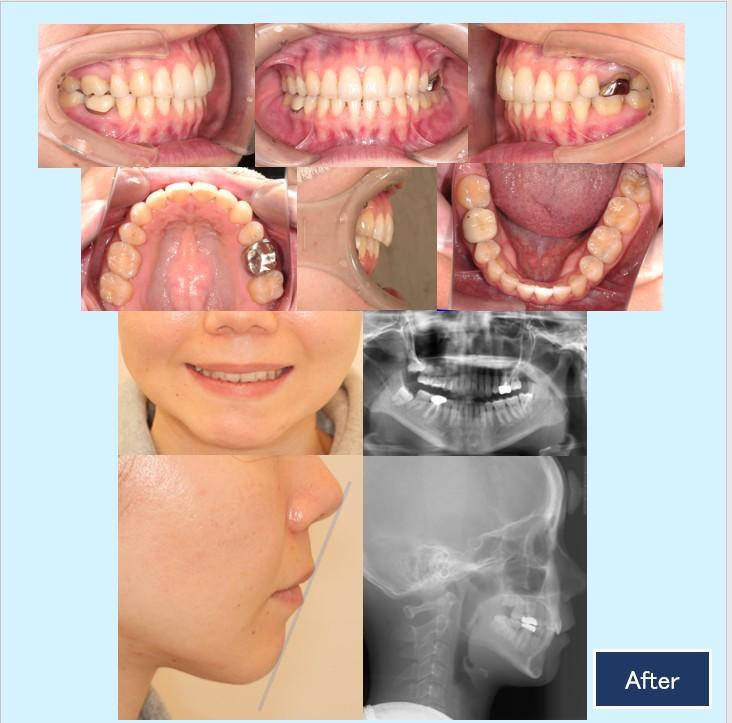

No.45 ハーフリンガルで治療した上顎前突症例

30代女性 千葉県習志野市

『①前歯を引っ込めて口が閉じやすく機能的な咬合にしたい』という主訴でした。

上下顎両側4番を抜歯して、上下顎前歯部を後方移動致しました。

上顎口蓋に歯科矯正用アンカースクリューを埋入し、ガミースマイルの改善をしました。

最終的な微調整では正中を出来る限り一致させる為に、顎間ゴムを使用して頂きました。

診断名:AngelⅠ級上顎前突症例

年齢:30代 治療期間:1年6ヵ月 治療回数:25回 初診時:2022年8月6日

治療に用いた主な装置:

◎歯科用アンカースクリュー

◎ハーフリンガル 上顎:カスタムメイド型リンガルブラケット矯正装置(WIN)下顎 プラスチックラビアルブラケット矯正装置

抜歯部位:上下顎両側4番

治療費:¥1,265,000-(通院費¥5.500別)

リスク・副作用:上顎前歯部突出+ガミーラインの改善は、歯科矯正用アンカースクリューから上顎前歯部を引っ張り、後方移動と共に少し圧下する必要があります。通常の後方移動よりも歯根吸収のリスクが大きいので、定期的にデンタル写真を撮影して弱く持続的な力で、注意深く矯正力をかけていきます。